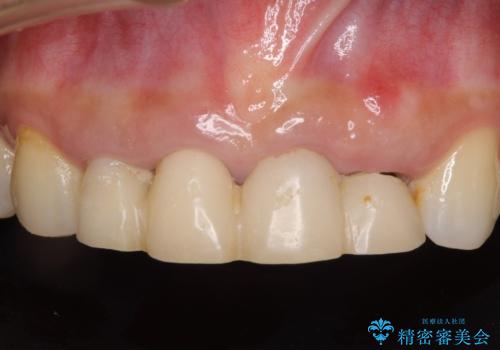

- 地元の歯科医院にて前歯4歯を仮歯に替えたものの、汚れていることが気になるとのことで来院された患者様です。

不適な仮歯の影響で歯肉が腫れていたため、新しい仮歯に替えた後に歯肉の腫れが引くのを待ち、オールセラミッククラウンにて補綴することとしました。

根尖病変が原因で、膿が出てきている歯があったため、仮歯を置き換える際に根管治療を行うこととしました。

仮歯を変えたことで歯肉の腫れは引き、根管治療も功を奏して膿の出口はきれいに消退しました。